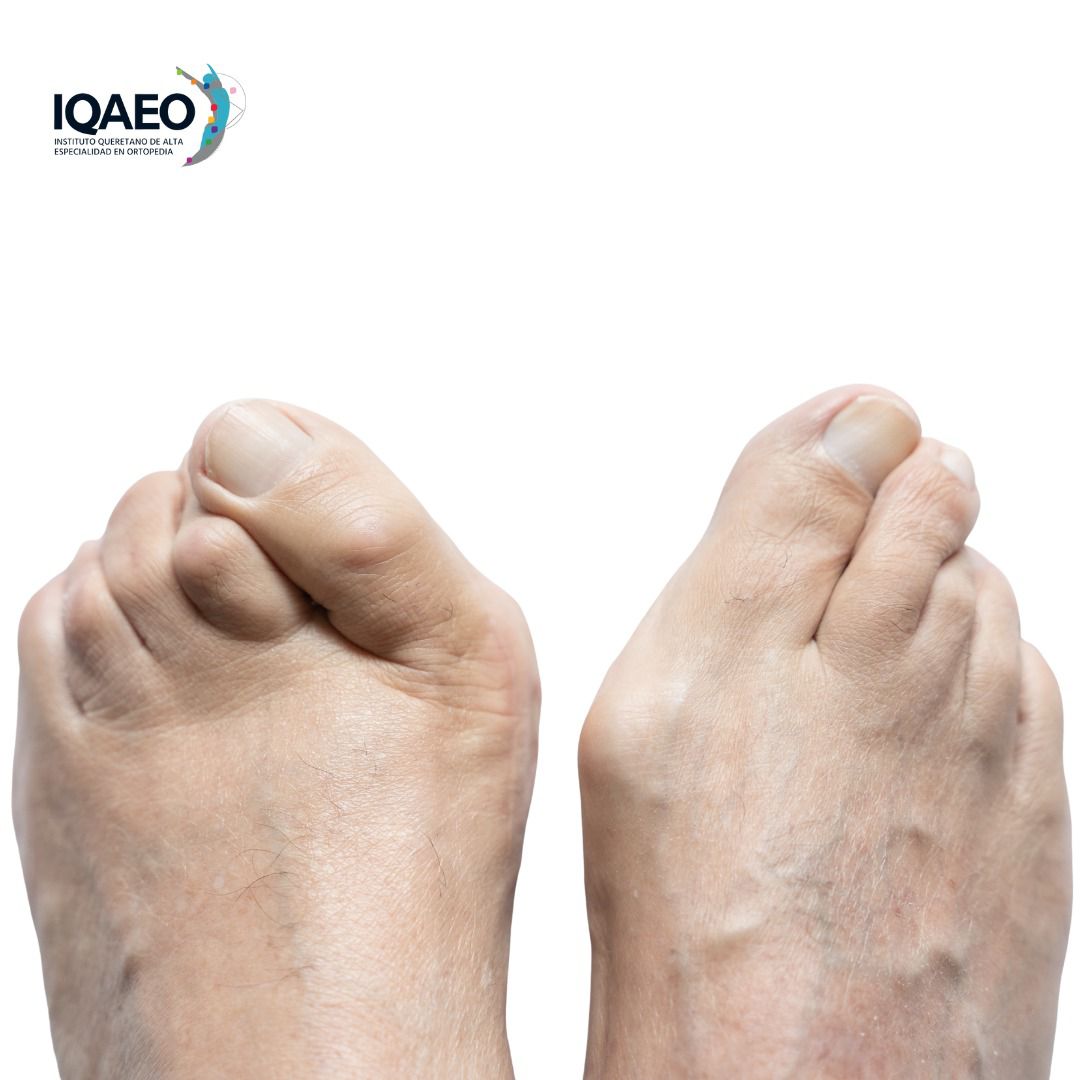

María y Carlos esperaban con ilusión a su primer hijo… de pronto conocieron a Rebeca en el hospital. A sus 25 años, cojeaba visiblemente y compartía su dolorosa historia: sufría desgaste en la cadera, deformación ósea y movilidad limitada. —Si tan solo me hubieran diagnosticado a tiempo —les dijo—. Si mis padres hubieran sabido lo que es la displasia de cadera…